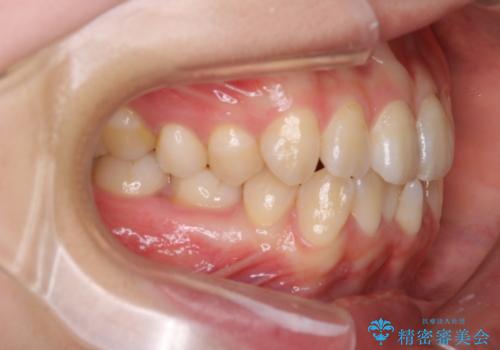

- 患者様は、右下第2小臼歯(5番)の先天欠如により乳歯が残存している状態でした。

診査の結果、乳歯は長期間機能していましたが、将来的な脱落のリスクが高く、インプラントによる永久歯の補綴が望ましいと判断しました。

また、欠損部にインプラントを埋入するには、前後の歯の傾斜改善とスペース確保のための矯正治療が必要でした。